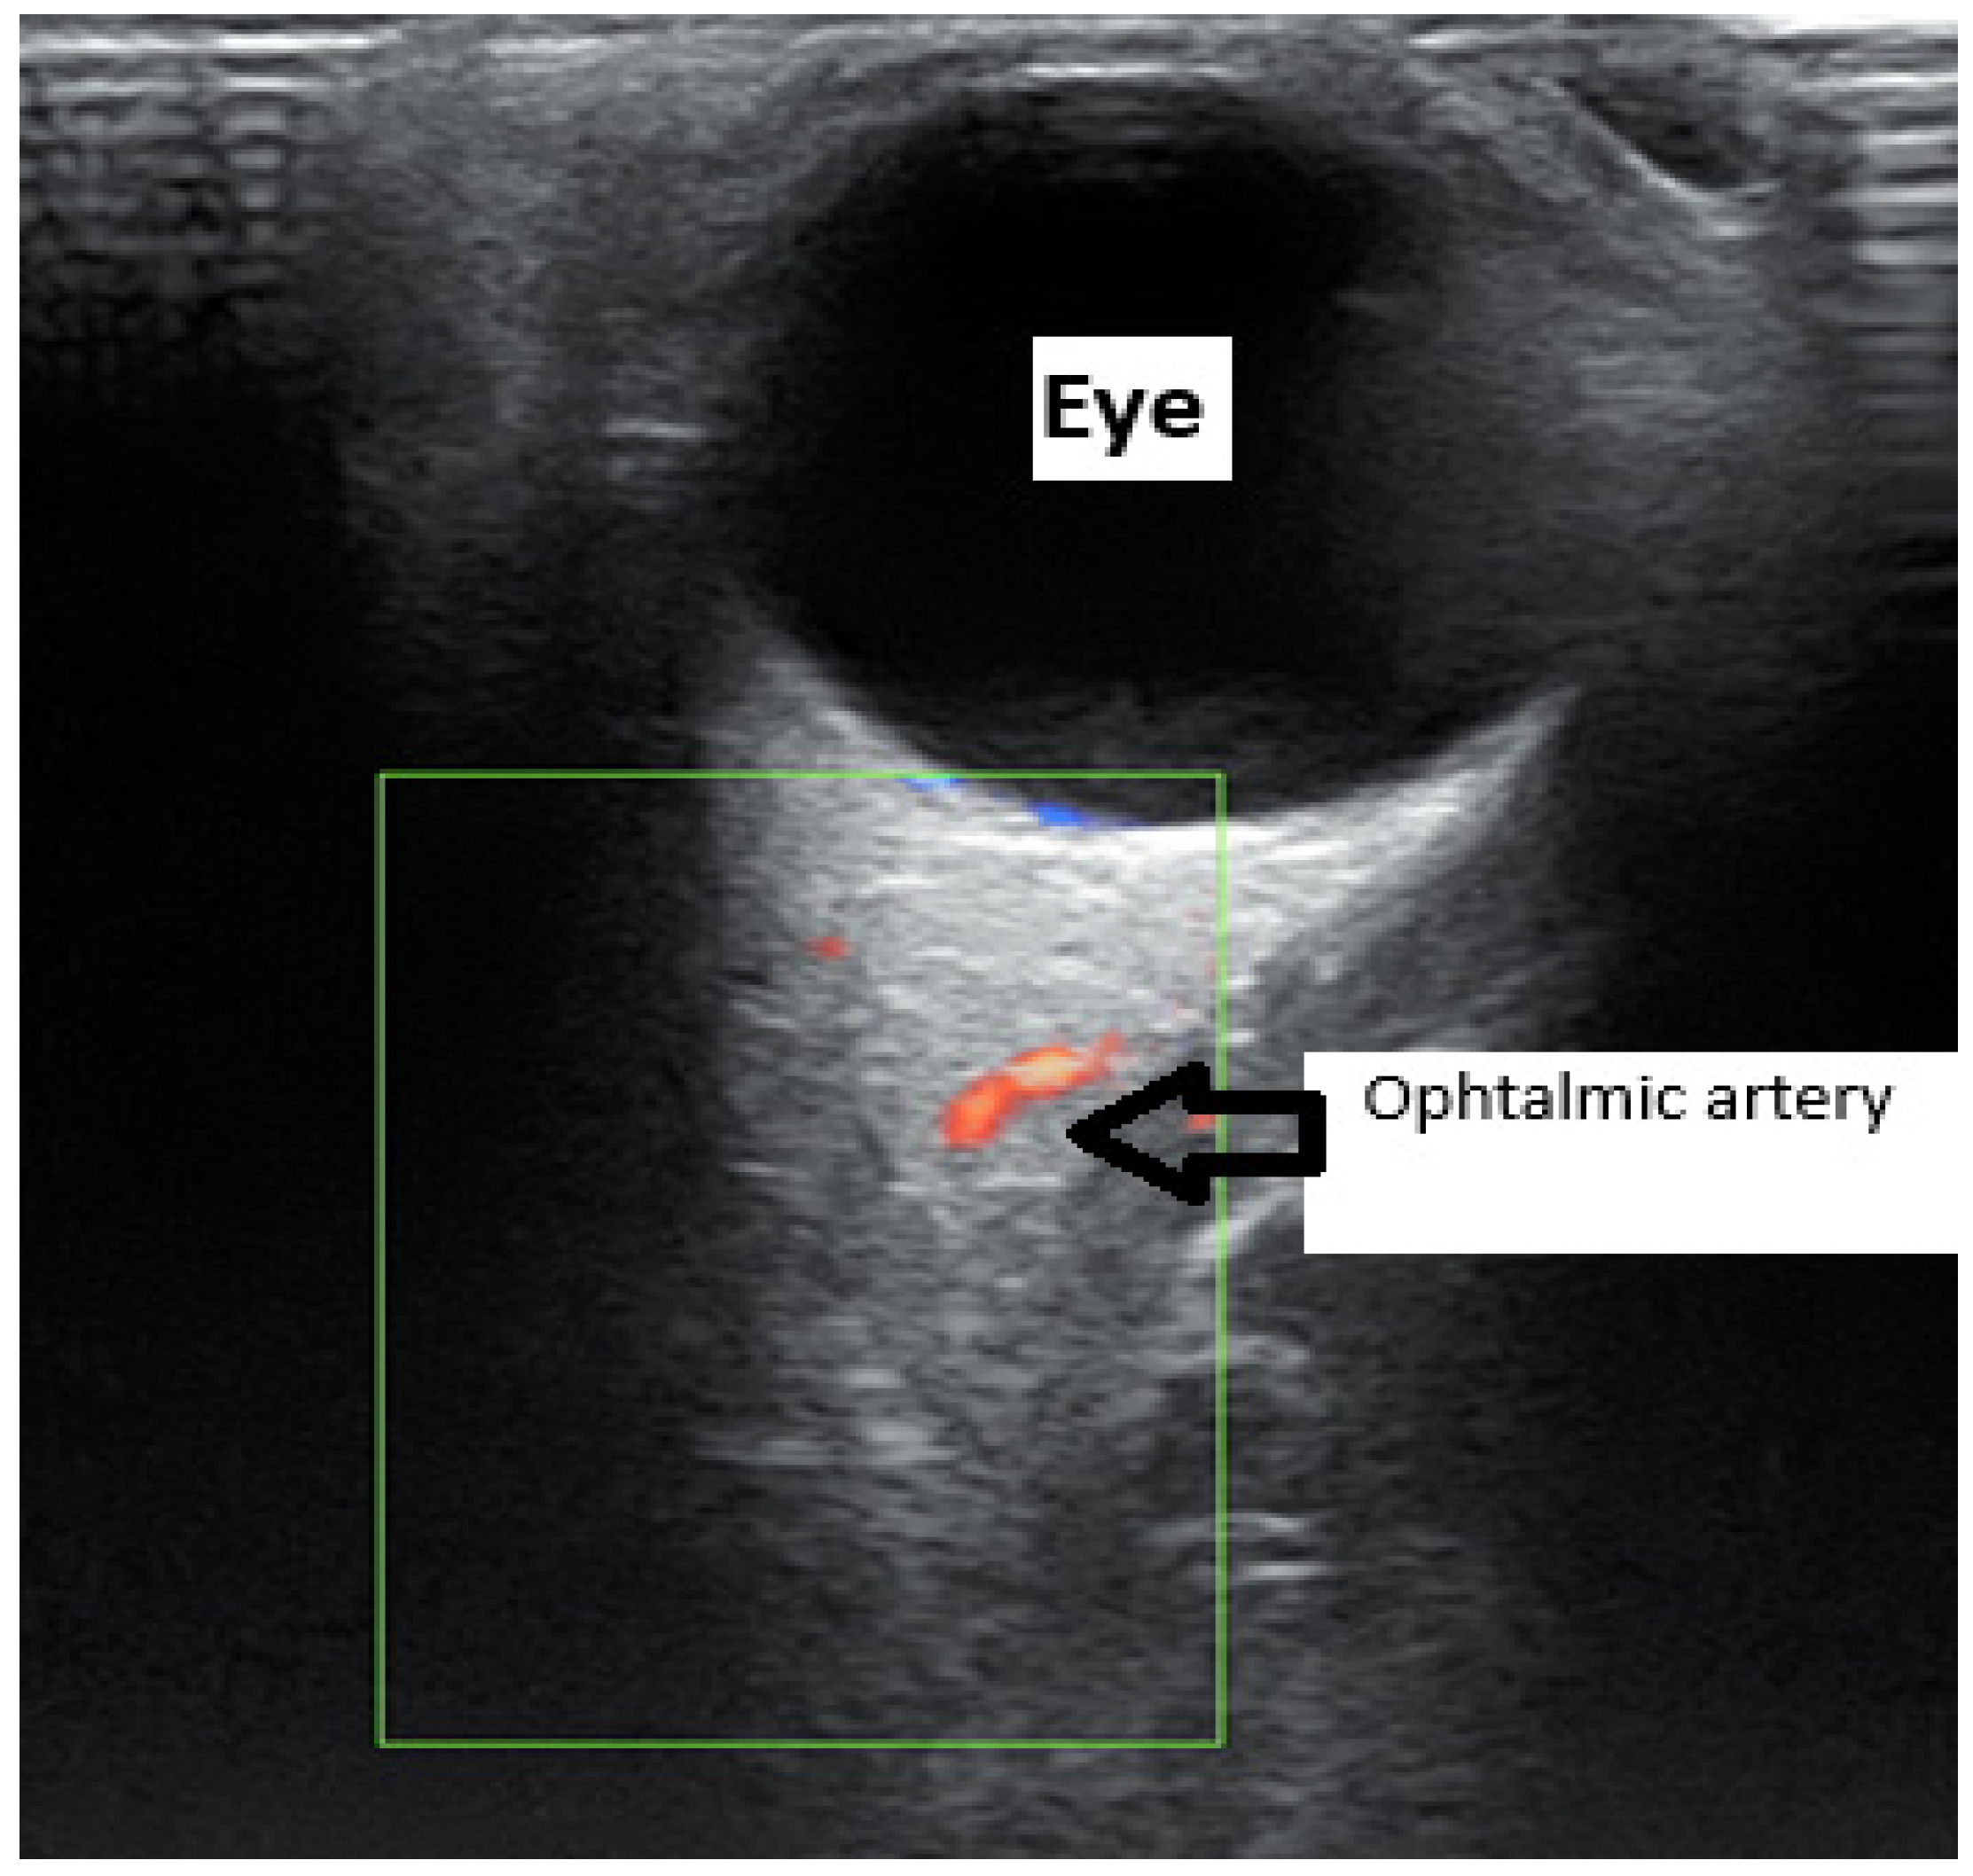

- Nicolaides, K.H.; Sarno, M.; Wright, A. Ophthalmic artery Doppler in the prediction of preeclampsia. Am. J. Obstet. Gynecol. 2022, 226, S1098–S1101. [Google Scholar] [CrossRef]

- Gurgel Alves, J.A.; Praciano de Sousa, P.C.; Bezerra Maia e Holanda Moura, S.; Kane, S.C.; da Silva Costa, F. First-trimester maternal ophthalmic artery Doppler analysis for prediction of pre-eclampsia. Ultrasound Obstet. Gynecol. 2014, 44, 411–418. [Google Scholar] [CrossRef] [PubMed]

- Praciano de Souza, P.C.; Gurgel Alves, J.A.; Bezerra Maia EHolanda Moura, S.; Araujo Júnior, E.; Martins, W.P.; Da Silva Costa, F. Second Trimester Screening of PE Using Maternal Characteristics and Uterine and Ophthalmic Artery Doppler. Ultraschall Med. 2018, 39, 190–197. [Google Scholar] [PubMed]

- Gana, N.; Sarno, M.; Vieira, N.; Wright, A.; Charakida, M.; Nicolaides, K.H. Ophthalmic artery Doppler at 11–13 weeks’ gestation in prediction of pre-eclampsia. Ultrasound Obstet. Gynecol. 2022, 59, 731–736. [Google Scholar] [CrossRef] [PubMed]